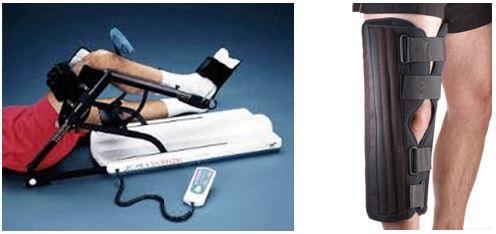

Ameliyat sonrası Rehabilitasyon:

Ön çapraz bağ tamirinde rehabilitasyon hastadan hastaya değişmektedir.

Bunun nedenleri; Tespitin sağlamlığı, kullanılan greftin tipi ve yerleşimi, Cerrahi işlemin tipi ve yaralanmaya eşlik eden diğer nedenlerdir.

Ön Çapraz bağ ameliyatı Kliniğimizde Profesyonel sporculara ve sporcu kimliği olmayan kişilere başarı ile uygulanmaktadır.

Ameliyat Artroskopik olarak(kapalı yöntemle) yapılmaktadır. Menisküs yırtığı veya başka ek lezyon bulunup bulunmamasına göre ameliyat ortalama 60-90 dakika arasında sürmektedir. Ameliyat sonrası hastalar rehabilitasyon için 3 gün kadar hastanede yatırılmakta, bu süre zarfında fizik tedavi uygulanmaktadır.